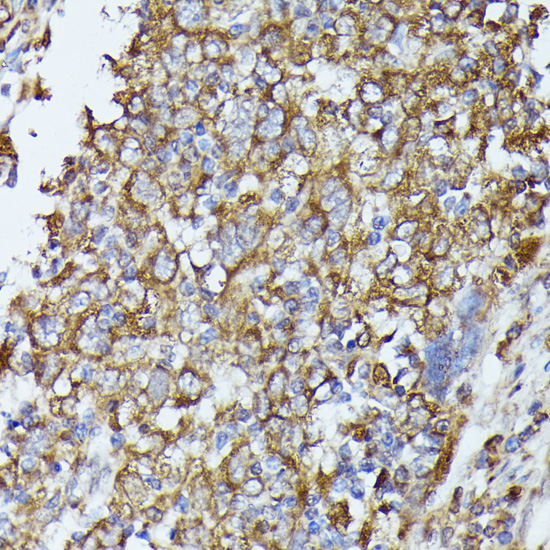

Immunohistochemistry of paraffin-embedded human esophageal cancer using TBCB at dilution of 1:100 (40x lens).

,